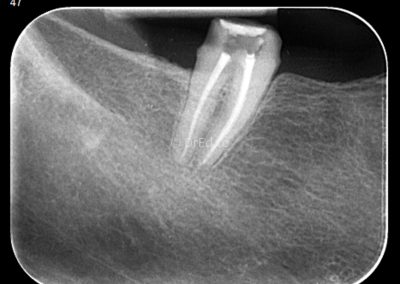

Galerie

Toate imaginile, fotografiile și radiografiile publicate pe acest site sunt protejate prin drepturi de autor și constituie proprietatea exclusivă a Dred.ro.

Aceste materiale sunt furnizate exclusiv în scop informativ și educațional și nu conțin date cu caracter personal sau informații care permit identificarea pacienților, în concordanță cu legislația privind protecția datelor cu caracter personal și GDPR.

Reproducerea, copierea, distribuirea, publicarea, transmiterea, modificarea sau orice altă utilizare, integrală ori parțială, a acestor materiale, în orice formă și prin orice mijloace, fără consimțământul prealabil scris al titularului drepturilor, este strict interzisă și poate atrage răspunderea civilă și/sau penală, în condițiile legii aplicabile privind drepturile de autor și protecția proprietății intelectuale.